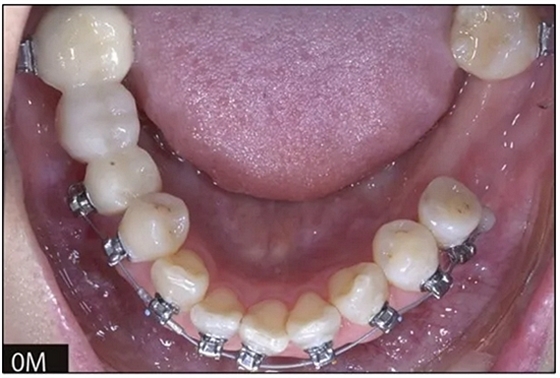

完全固定的Damon Q設備(加利福尼亞州Glendora的Ormco)與制造商指定的弓絲和附件一起使用。下頜弓,一開始放入0.014英寸的鎳鈦弓絲,5個月后放入0.014×0.025英寸的鎳鈦弓絲。舌側扣和鏈圈放置在下頜尖牙和第二前磨牙上以控制扭轉。在治療的第7個月,將下頜弓絲換成0.017× 0.025英寸的β鈦絲。另一個舌側扣和鏈圈放置在下頜左側第三磨牙上以提供近中牽引力(圖9)。在16個月的治療結束時,所有的扭轉都得到了矯正,缺牙間隙縮小到8 mm(圖8),但由于頰側骨板的嚴重吸收,牙槽嵴的寬度仍然很窄(約3 mm)(圖9)。通過正畸移動下頜左側第二前磨牙,在前磨牙之間產(chǎn)生一個種植部位。在第一和第二前磨牙之間的弓絲上放置一個推簧,并將舌側扣和鏈圈放置在第一前磨牙和第三磨牙之間(圖9),在頰側和舌側施加力。施力均為輕力,每個表面上約2盎司(28.3 cN)以控制牙根側面的吸收。

圖8

圖9